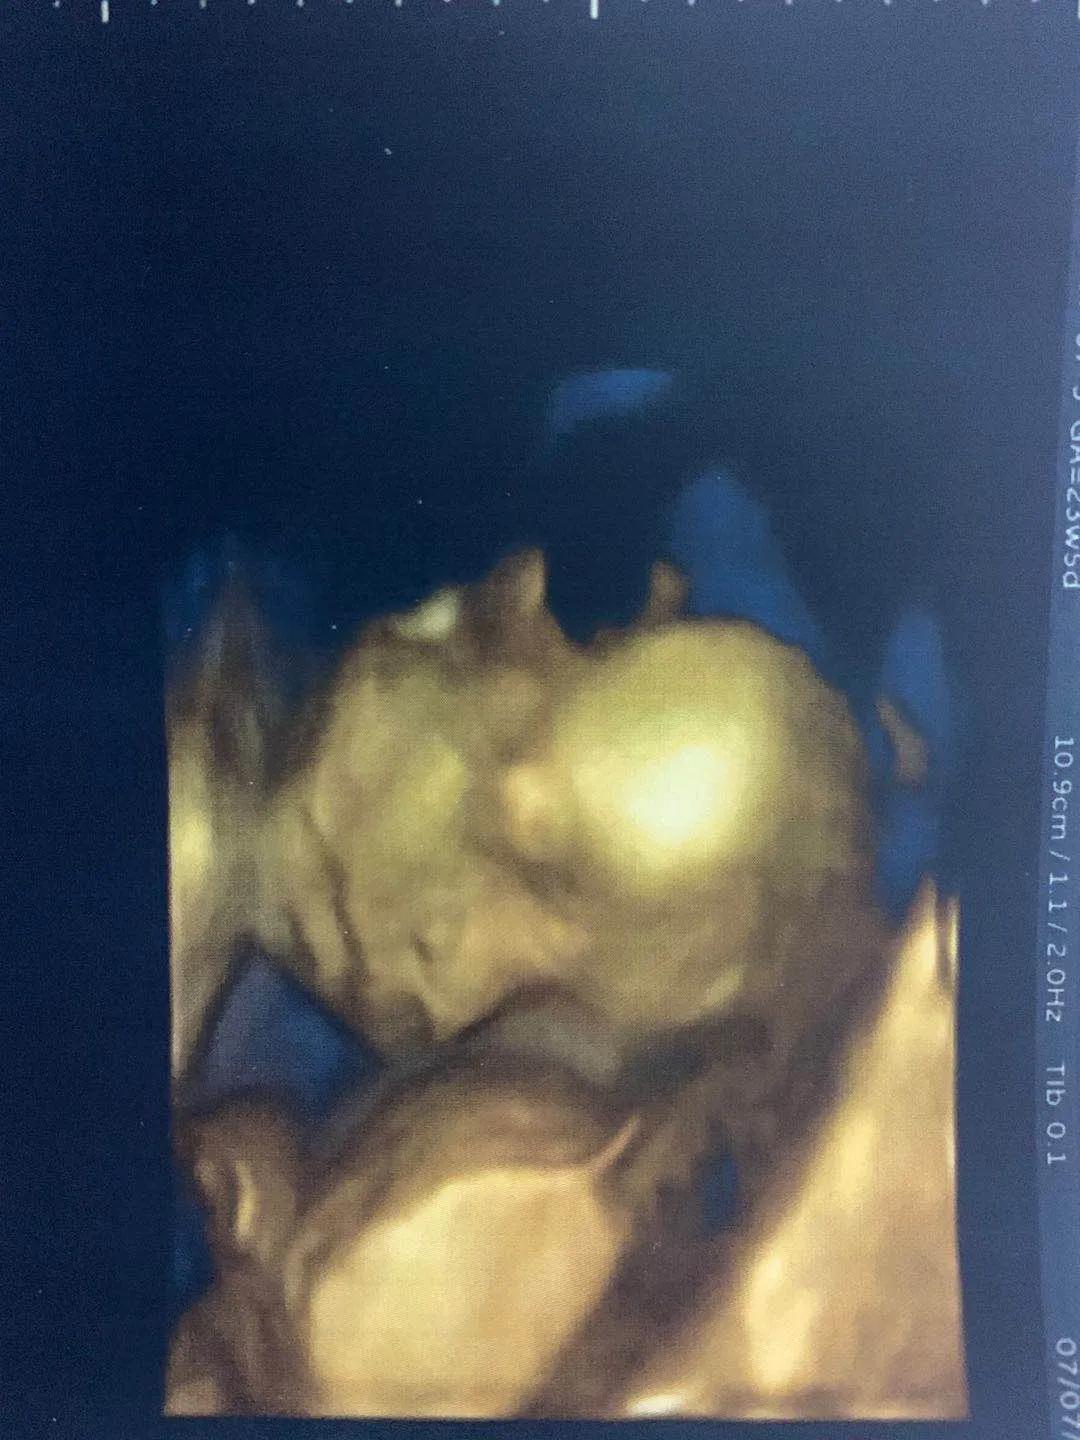

小排畸顺利通过,看到宝宝在肚子里的照片,感觉好奇妙好可爱好幸福,之前打针吃药的苦都是值得。